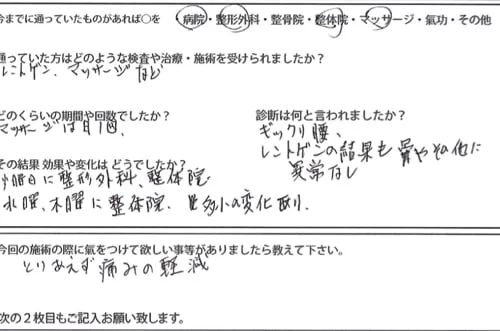

痛みが出ている場所はこの辺り

反対側も痛みがあり

お尻付近も痛みが出ていて

左足の太腿にも痛みが出ていました。

横になっても、寝返りも痛みが出て辛い状態です。

実際にお身体の状態を診させて頂くとこんな感じでした。

赤い線は筋肉や腱の硬直やヨジレ。Xは痛みの強い場所

✔は痛みが気になる場所です。

今回の「ぎっくり腰」の原因は

腰ではなく腹筋関連の硬直が大きな原因の1つ

そしてもう1つは太腿の硬直でした。